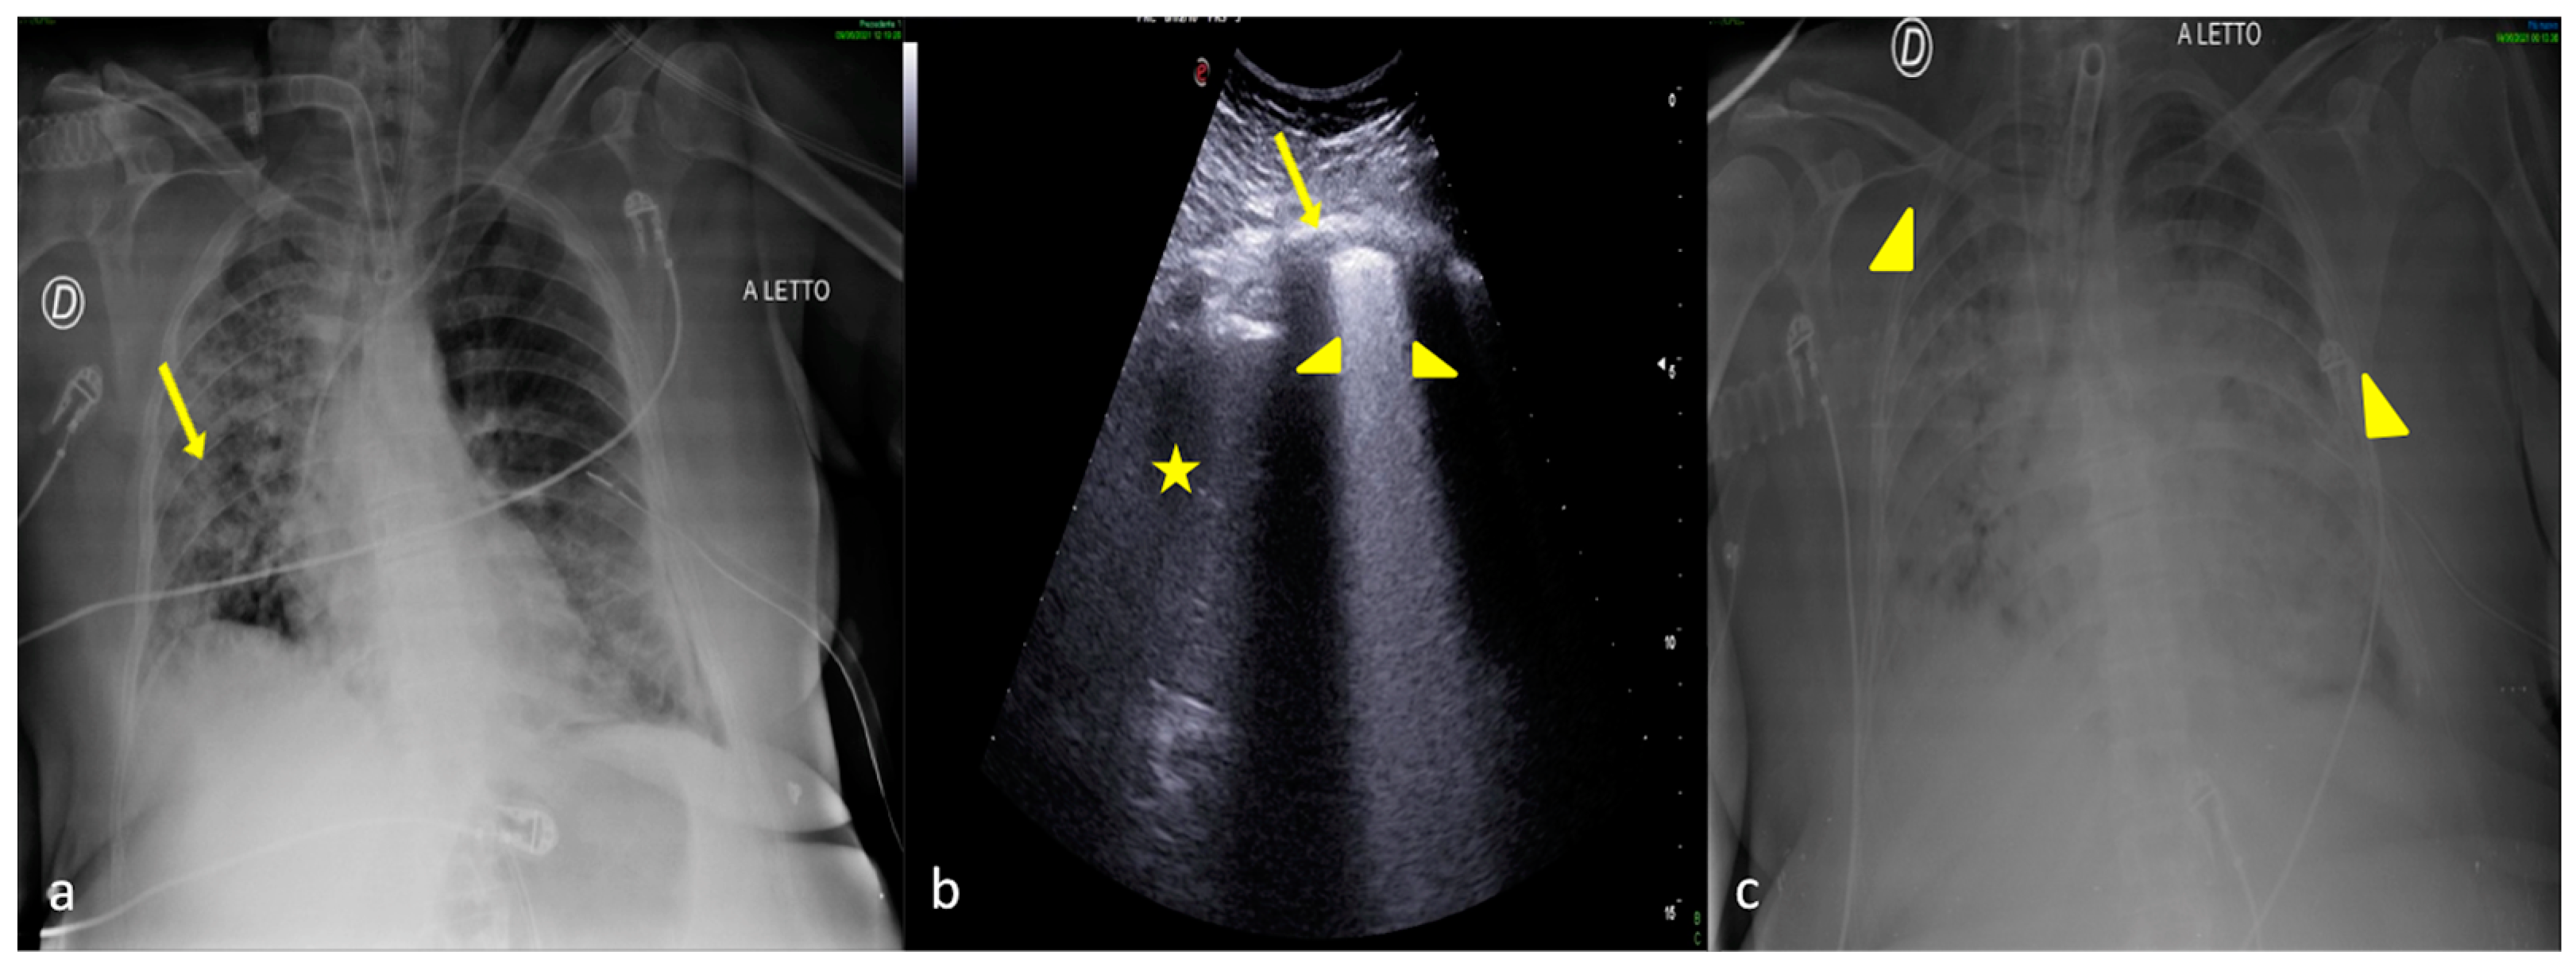

2.1. Atelectasis